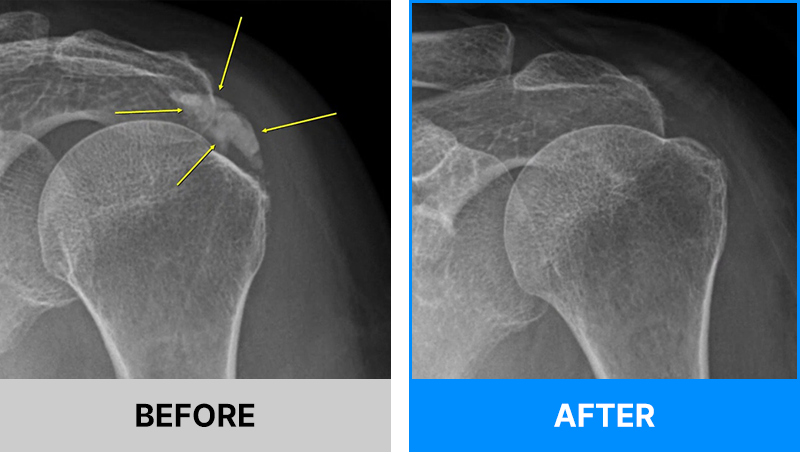

어깨의 석회는 그 시기에 따라 액체형과 고체형 그리고 혼합형으로 존재할 수 있습니다.

액체형 석회를 흡인하는 것은 어디에서나 가능합니다. 하지만 고체형 그리고 혼합형 제거에는 많은 노하우가 필요합니다.

서울거탑정형외과에서는 고체형 석회를 잘게 분쇄하여 뽑아내는 독자적인 기술과 노하우를 보유하고 있습니다.

형성기/휴지기의 고체형 석회

흡수기의 액체형 석회

해당 시술은 석회의 위치를 초음파로 정확히 확인한 뒤,정교한 기술로 진행되는 비수술 치료입니다.

그만큼 의료진의 숙련도와 경험이 매우 중요하므로, 풍부한 시술 경험을 가진 정형외과 전문의를 통해 치료받는 것이 좋습니다.

서울거탑정형외과에서는 풍부한 노하우로 초음파를 통해 정확히 석회를 확인 후 고체형일지라도 미세하게 분쇄하여 제거가 가능합니다.

95%이상 석회 제거가 가능합니다.